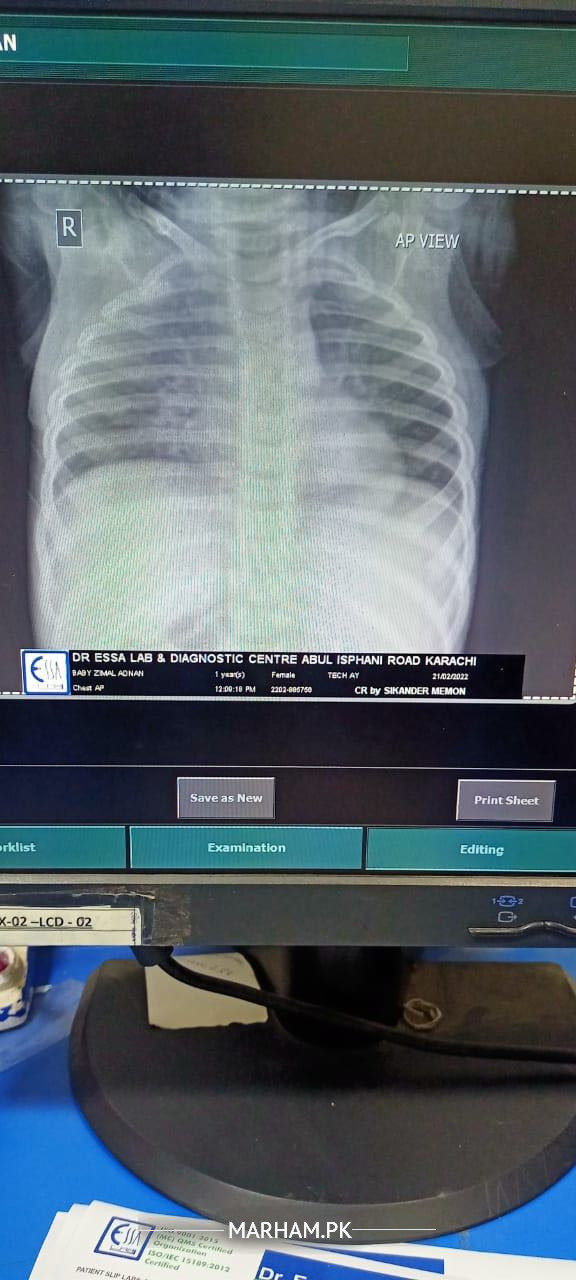

Blood culture nai karaya ige crp and cbc esr profile karaya hai and chest xray. Cbc esr report and chest xray pictures are attached. Waiting for remaining reports

Xray